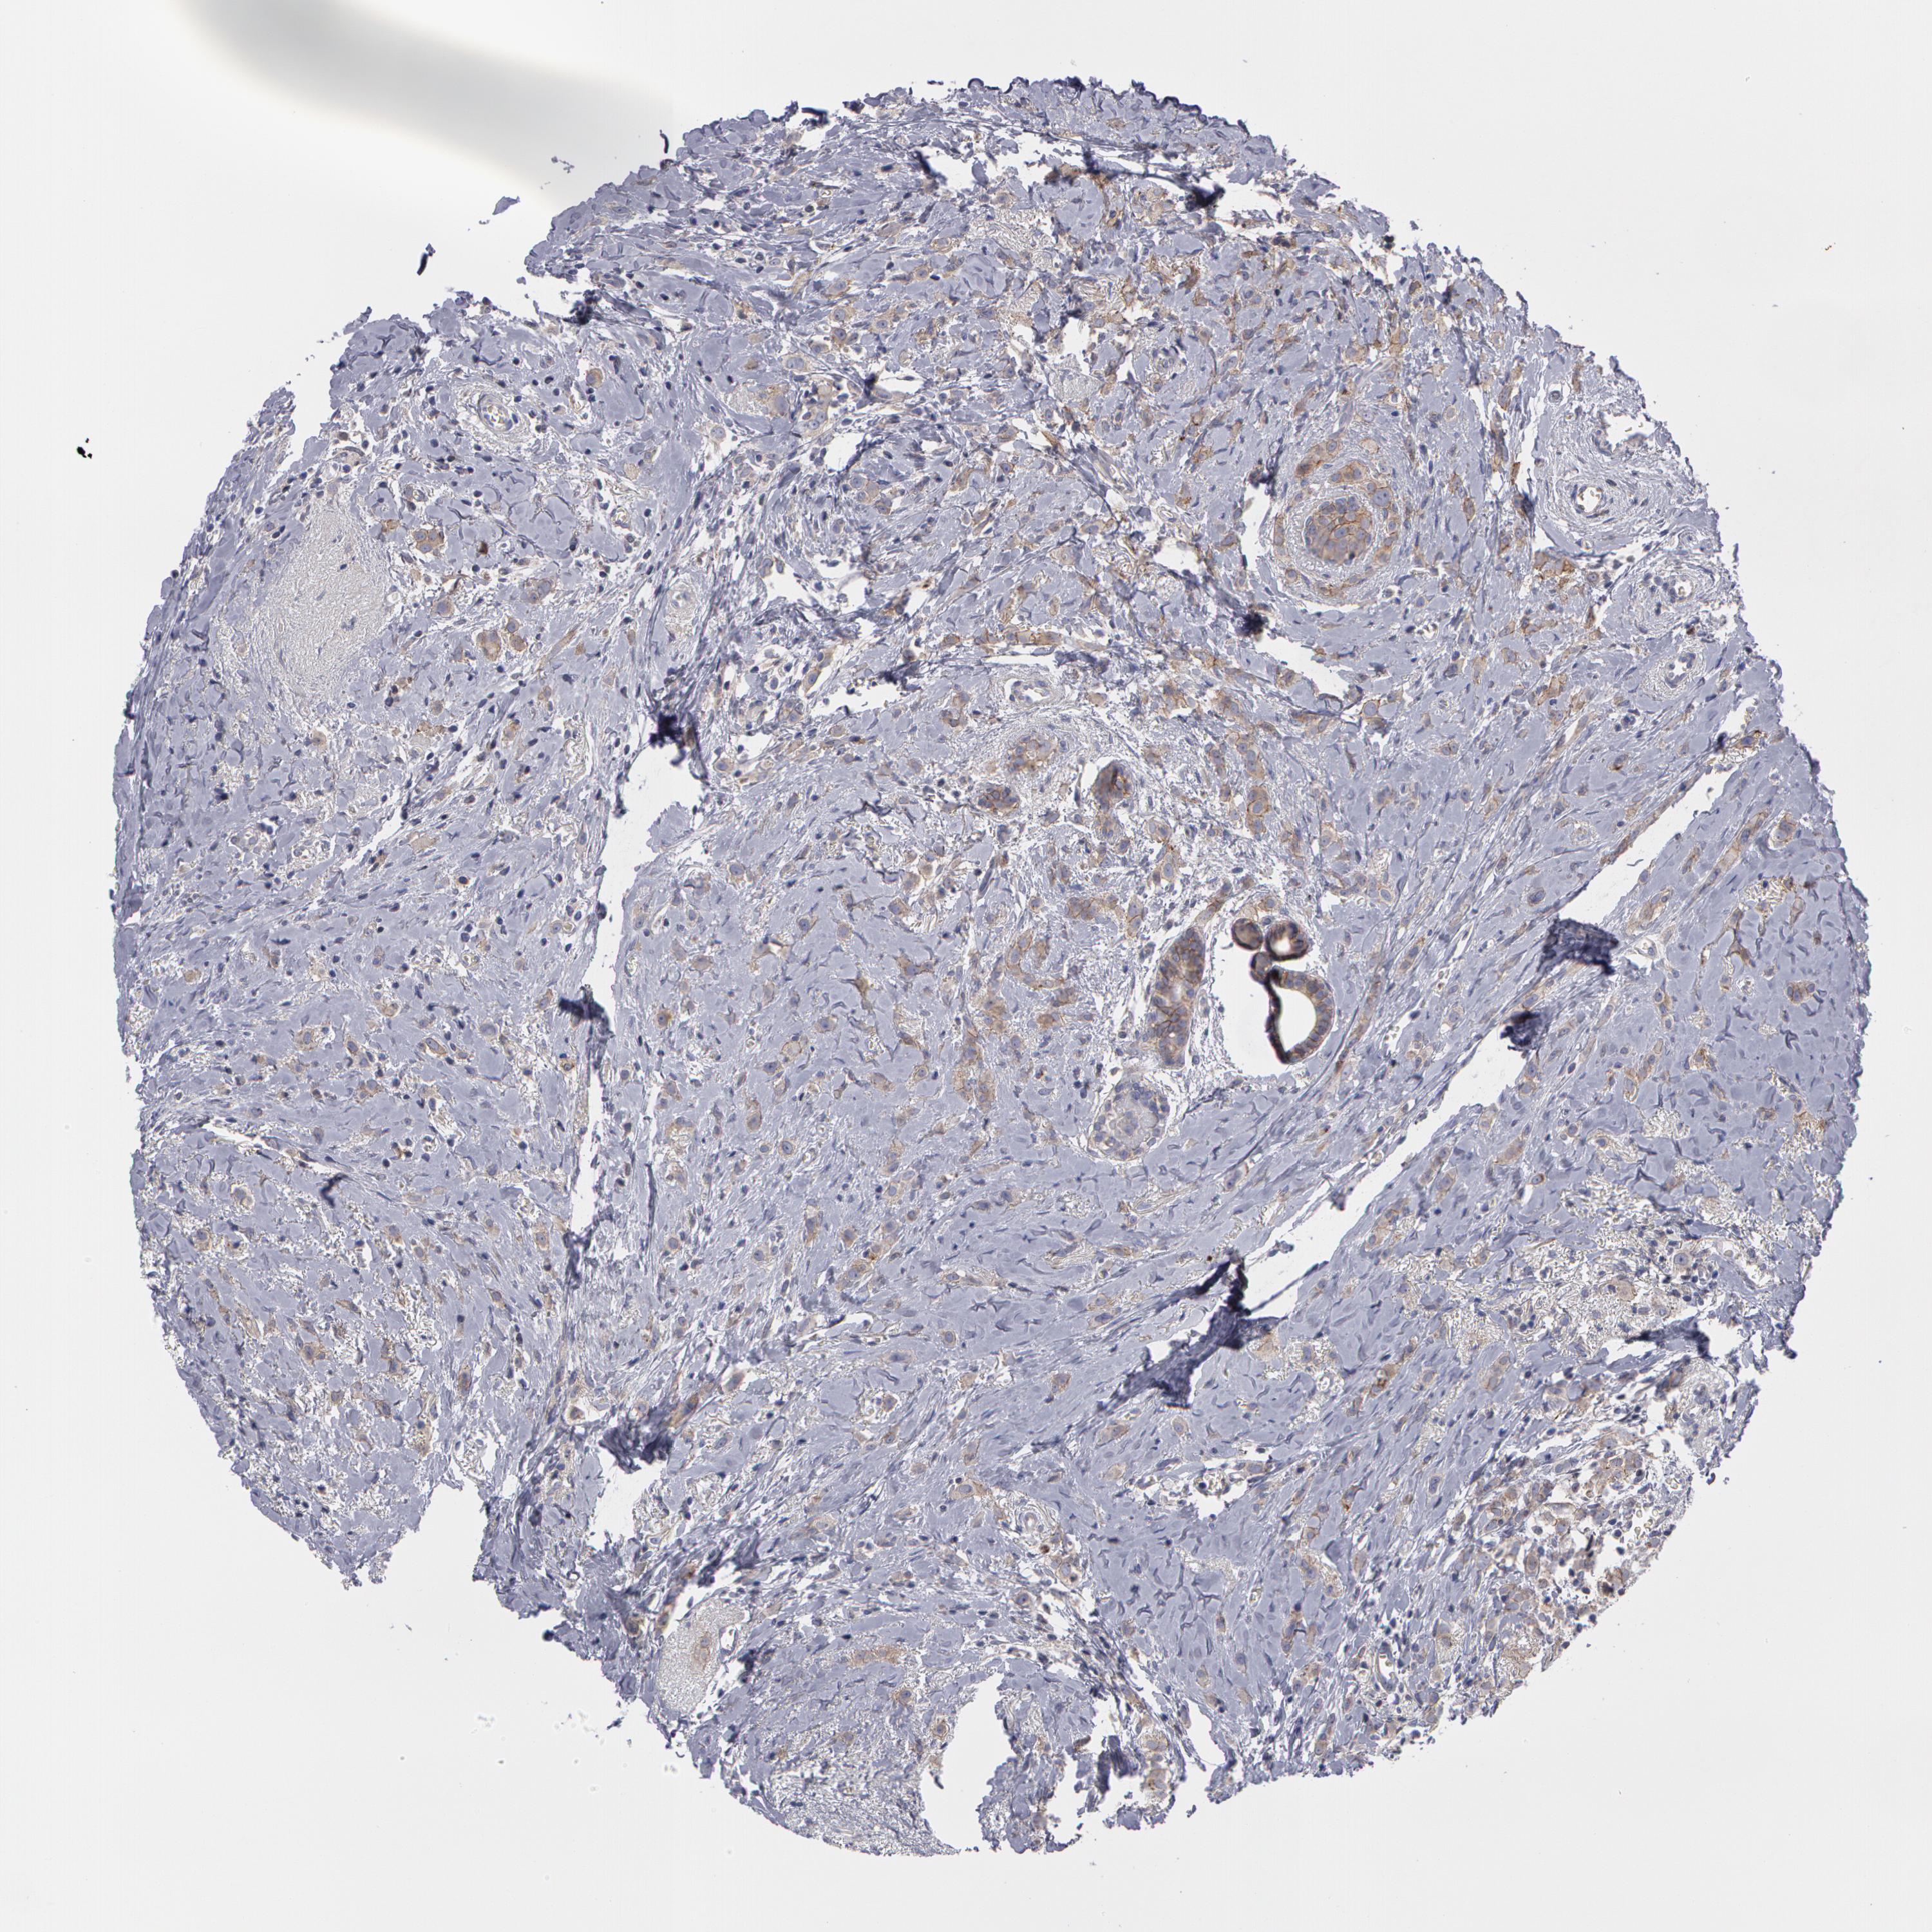

BRCA TCGA BRCA VALIDATION PROTEIN EXPRESSION

ANTIBODIES

AND

VALIDATION